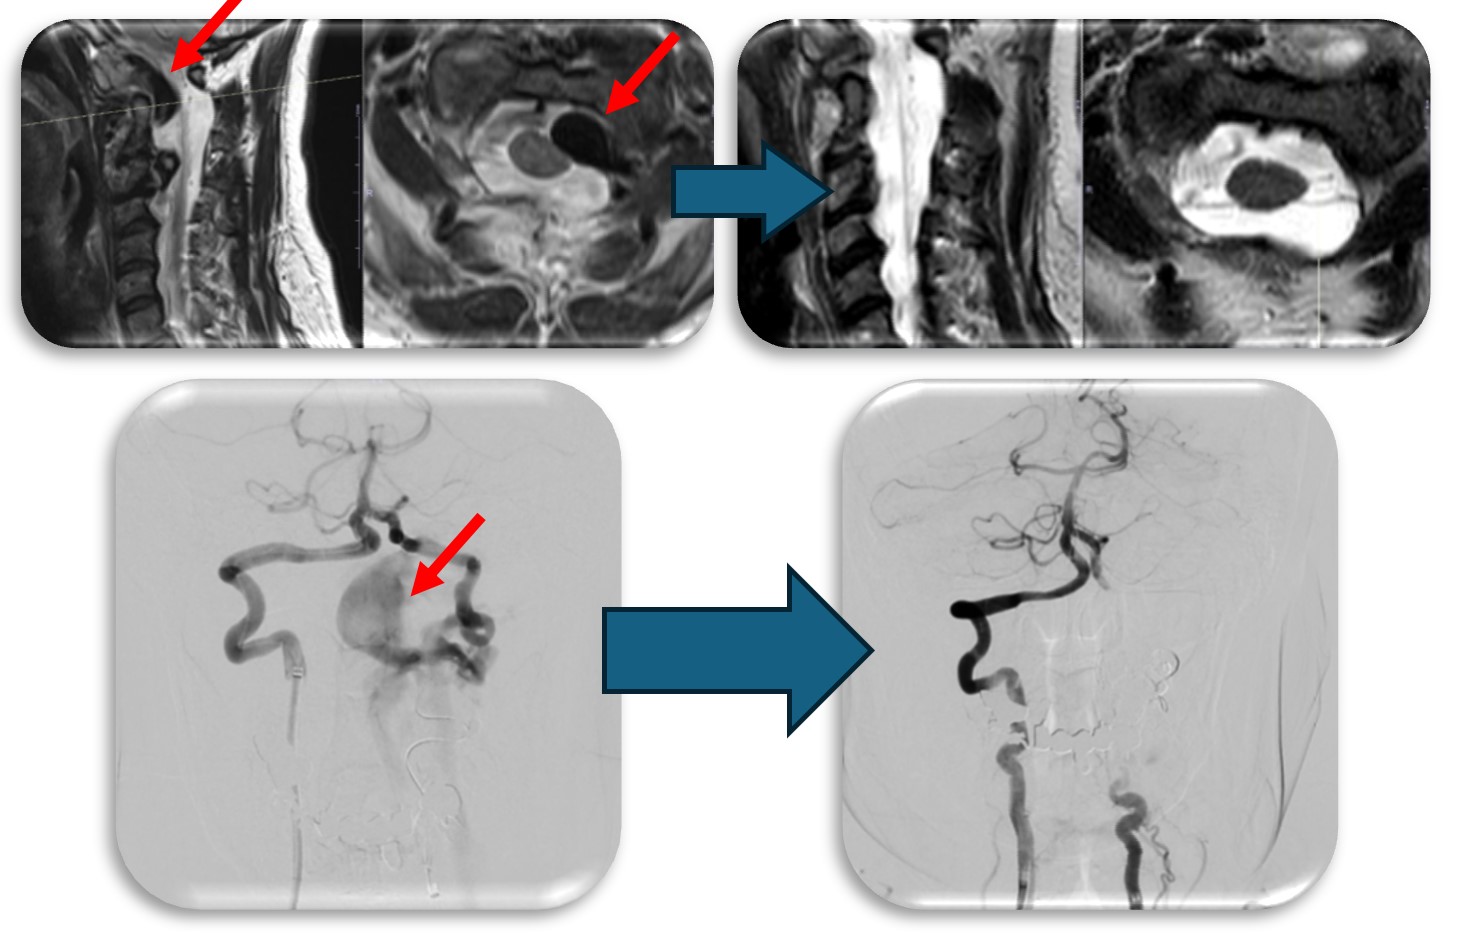

(代表例③)

腰部の脊柱管狭窄症に対して、腰の側方から徐圧し、後方から固定術(OLIF)した症例です。椎間板が摩耗していたり、不安定性がある症例、後方からの手術歴があり再手術症例に適した手術方法です。狭小化した椎間板にスペーサーを挿入(白線)する事により、脊柱管の高さを正常な状態に戻し3次元的に狭窄を改善させます。